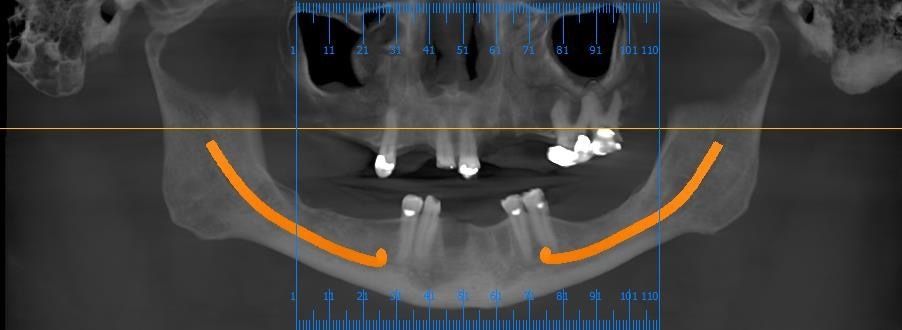

This image shows a detailed analysis of the bone condition around the extraction sites,

including buccal and lingual bone width and the shape of the alveolar ridge.

Such data serve as essential reference points when establishing an implant treatment plan after extractions.

This view shows the analysis used to determine the optimal positions,

angulations, and depths for implant placement in both the maxilla

and mandible in a fully edentulous case.

In the maxilla, the location of the maxillary sinus is a key factor,

while in the mandible, the position of the inferior alveolar nerve canal is critical.

If the bone quality is insufficient,

bone grafting may be required to achieve stable implant placement.